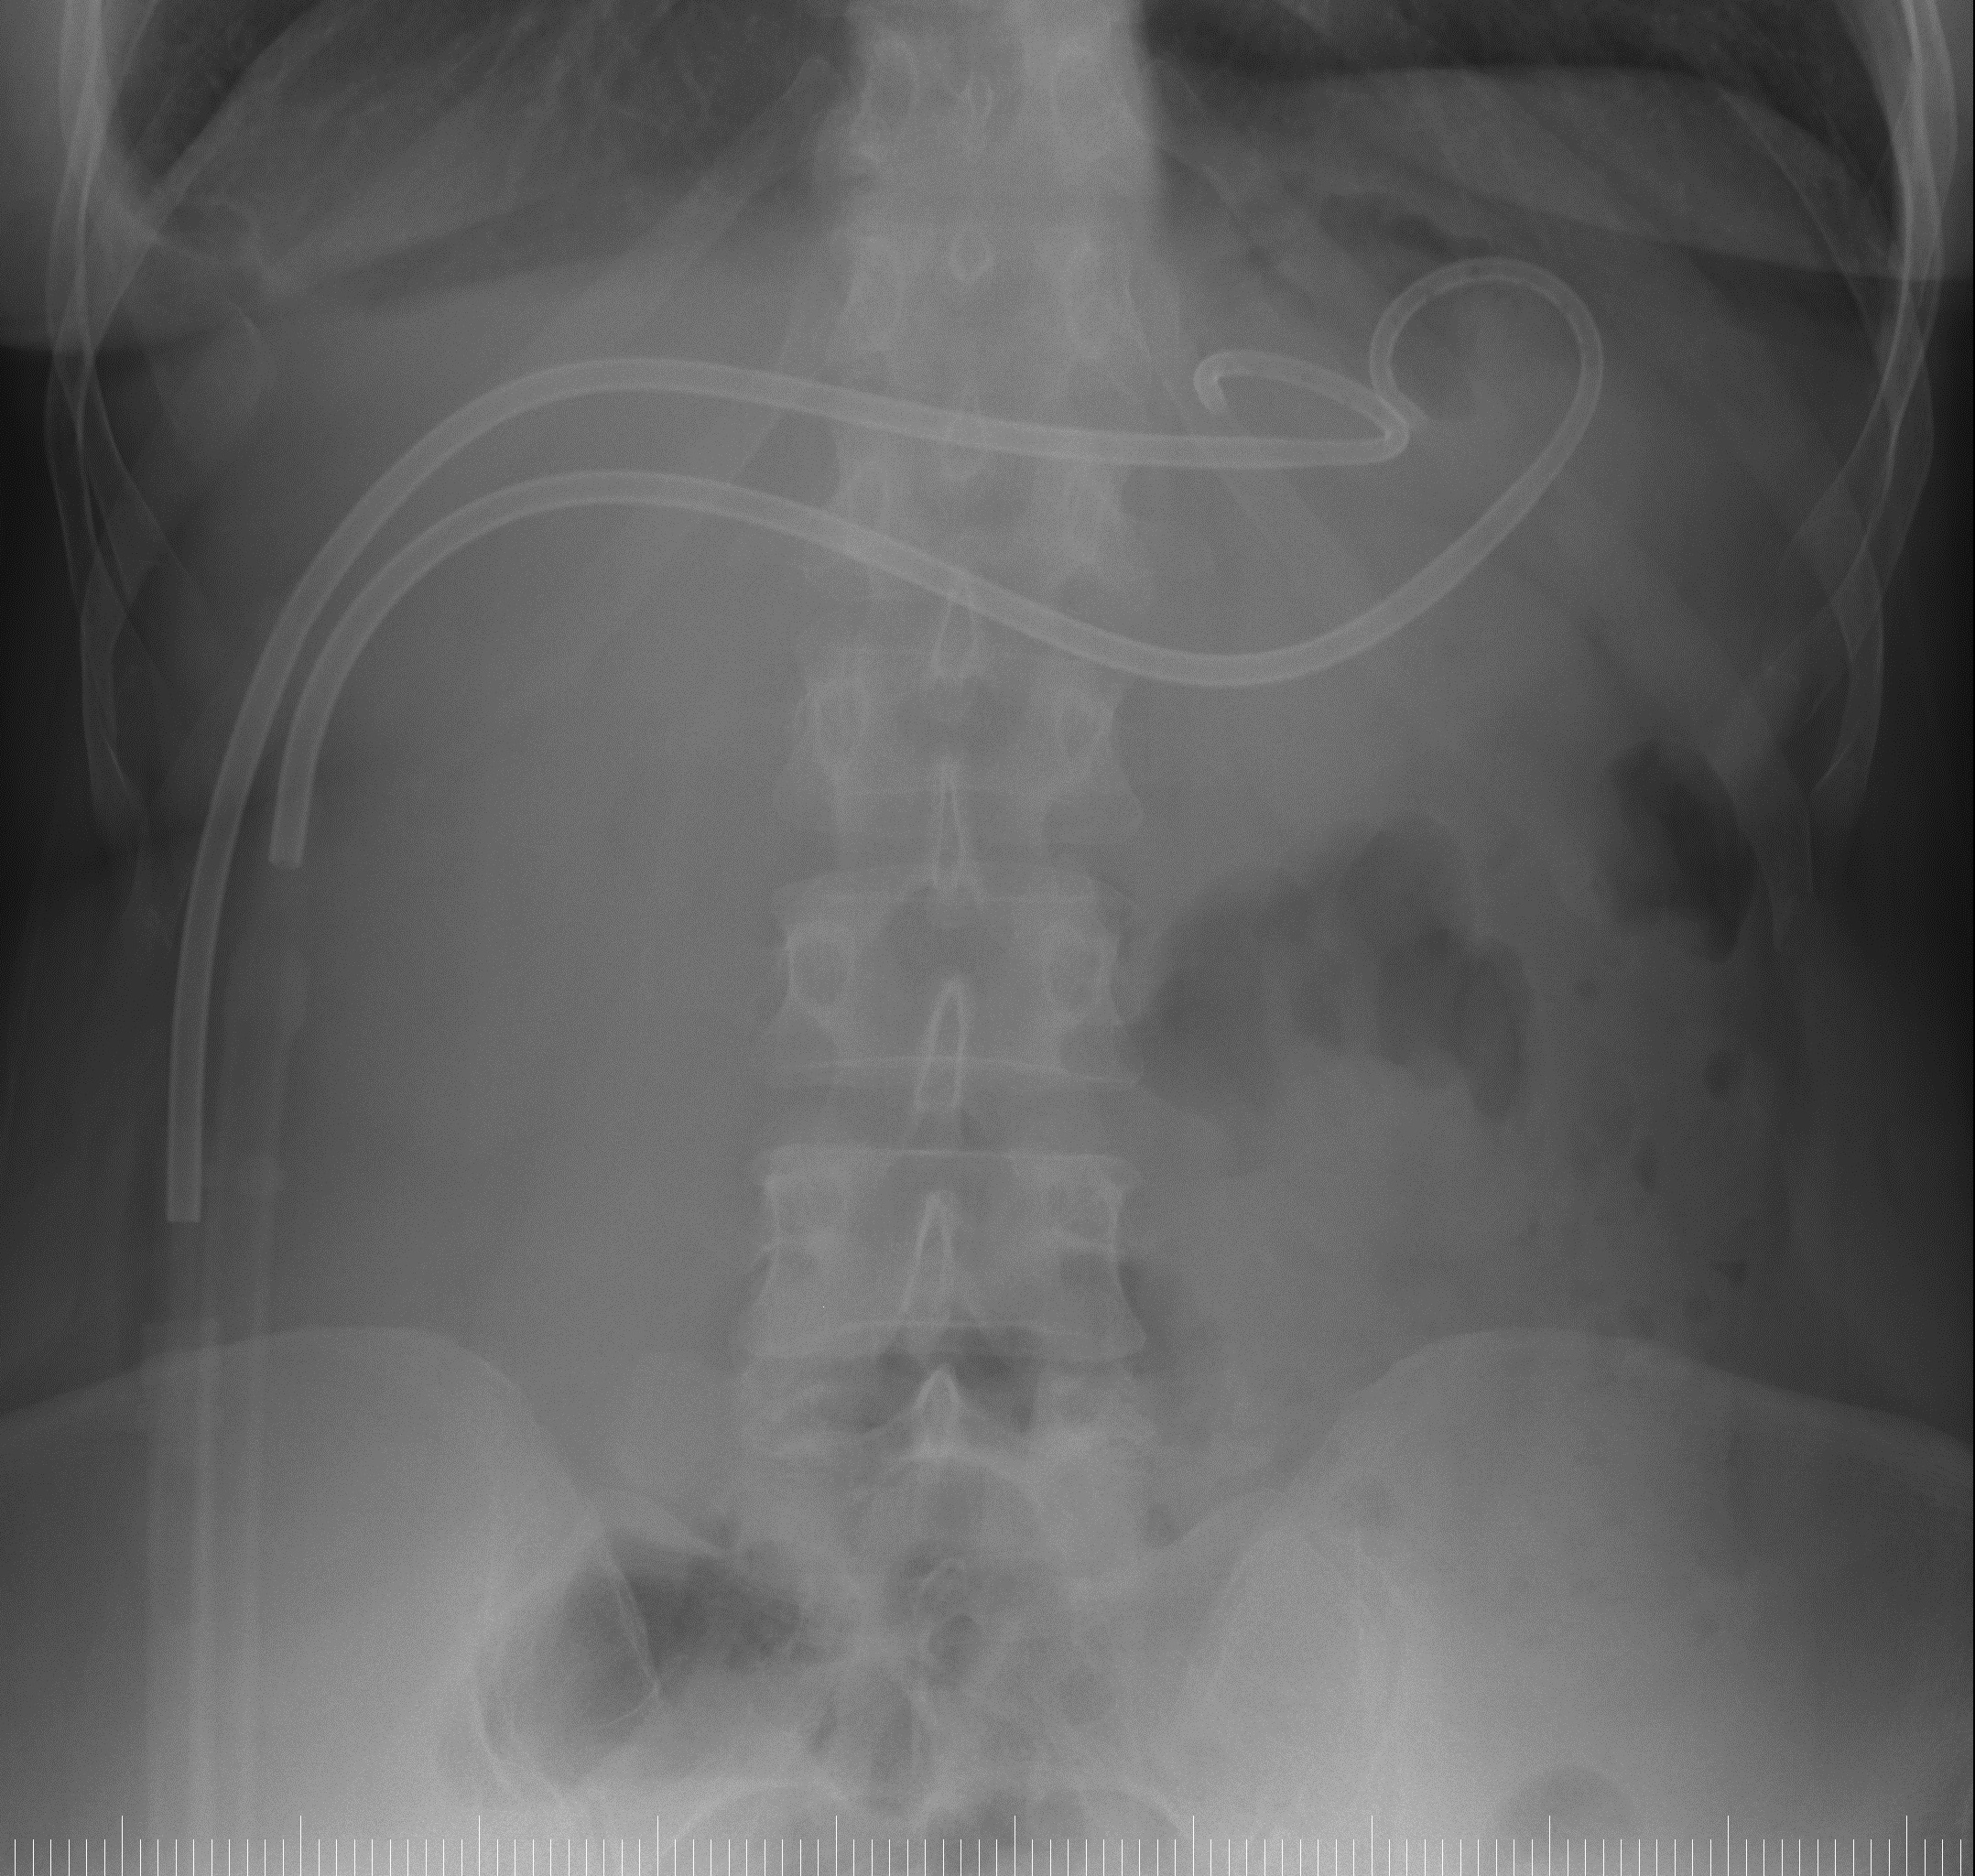

При рентгенфистулографии определяются две трубки в полости кисты с неоднородным содержимым (фрагменты разрушенных фрагментированных хитиновых оболочек):

Затека контрастного вещества за пределы полости кисты не выявлено.

Под рентгентелевизионным контролем выполнена замена одной трубки на более широкую 18F с кончиком pig-tail.

При контрольной рентгенфистулографии определяются две трубки в полости кисты с практически однородным содержимым (сохраняются единичные фрагменты разрушенных фрагментированных хитиновых оболочек) и через тонкий субсегментарный желчный проток от верхнего края полости заполняются контрастом желчные протоки с беспрепятственным сбросом в 12п.кишку:

Ежедневно проводилось отмывание полости кисты от остатков хитиновой оболочки. Поступления желчи в трубки практически не отмечалось (легкое прокрашивание промывных вод). После отмывания полости кисты через несколько дней при рентгенфистулографии определяются две трубки в уменьшившейся в размерах остаточной полости кисты с однородным содержимым. Поступления контрастного вещества в желчные протоки не отмечается: